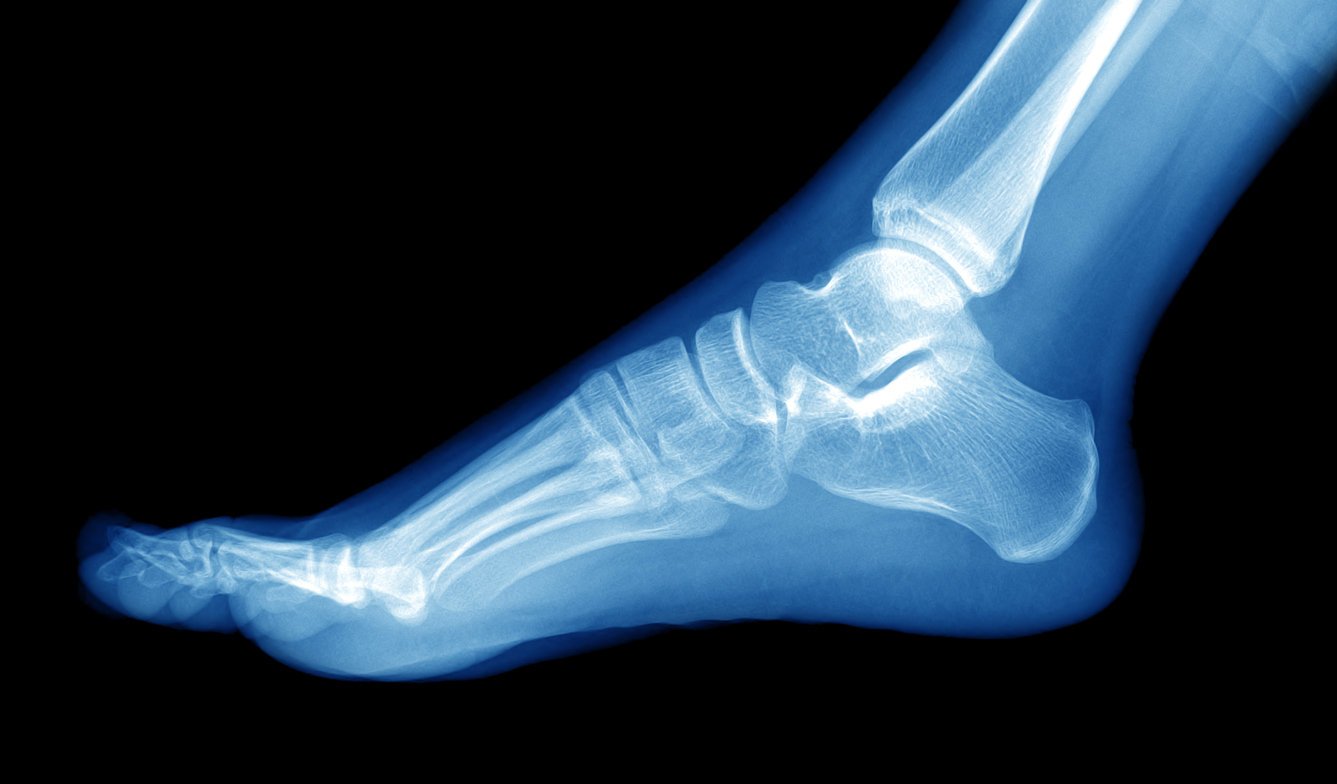

x-ray of foot human

Istock

Le diagnostic repose sur l’imagerie : la radiographie permet de visualiser l’épine tandis que l’échographie montre son origine et permet de la localiser de manière précise. "Une épine peut-être présente en radio sans que le patient est mal, cela arrive de temps à autre", affirme le podologue Alexandre Saussier.